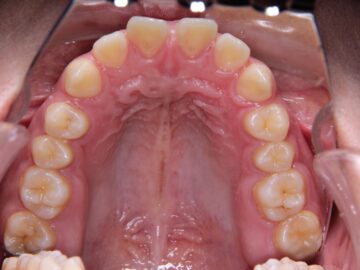

治療後